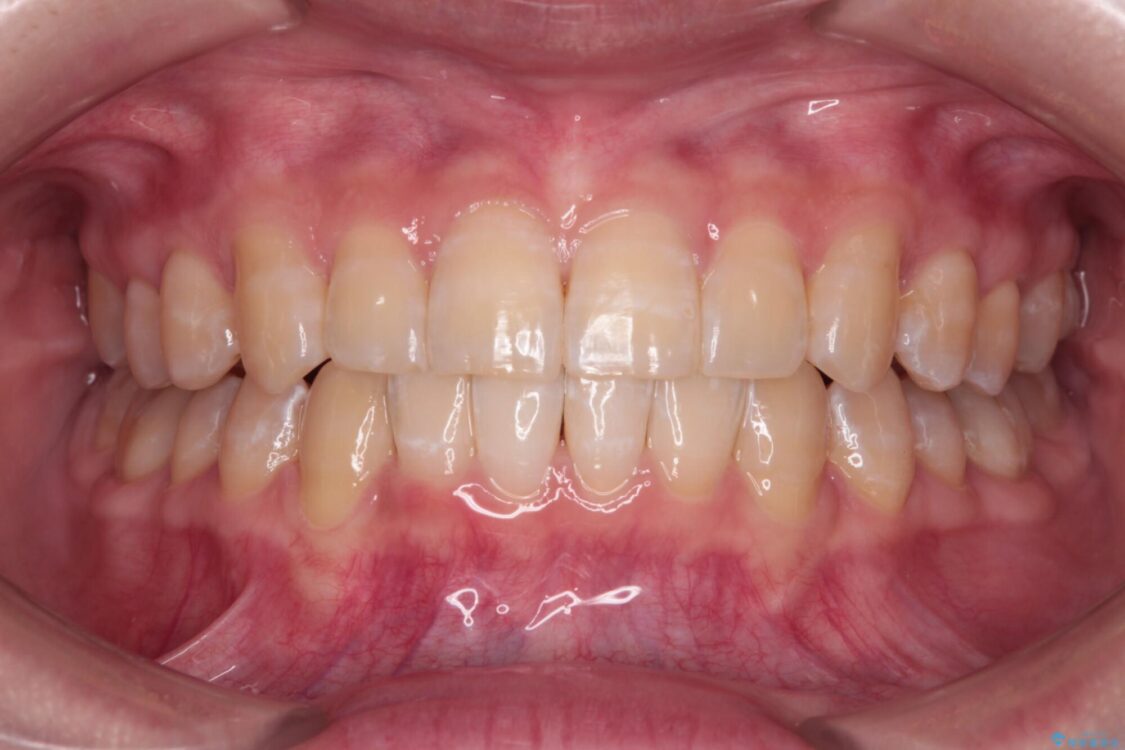

治療後について

治療前、下顎前歯のデコボコが集中しており、奥歯の咬み合わせは、上顎に対して下顎が前方位にある状態でした。下顎の歯列を後方へ移動させる治療はインビザラインの得意とするところですので、1年程度で無事に治療を終えることができました。

治療後

• 【モニター】下顎前歯のデコボコをインビザラインできれいに 治療後画像